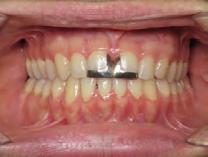

4). Archwires were upgraded incrementally into 19 x 25 SS. Once the bite was completely closed, the patient was referred to the myofunctional therapist to begin treatment. Eight sessions of myofunctional exercises were performed, focusing on muscle building, toning, synchronicity and awareness. Improvement in correct chewing, swallowing and resting postures of the lip and tongue were addressed. All appliances were removed 21 months after initial insertion (Figure 5), and the patient was referred to a re-

storative dentist for veneers on the maxillary central incisors; the patient opted for gold veneers (Figure 6). Clear removable retainers were inserted with a fixed mandibular retainer canine-to-canine.

Treatment Results

The patient finished with Class I occlusion, ideal overbite and overjet. The arches are co-

Figure 5. Final records.

ordinated, lateral open bite closed and occlusal cants leveled. From the frontal cephalometric tracings, maxillary width increased from 58 mm to 69 mm. From the lateral cephalometric tracing, the incisor angulations remained unchanged. The final report from the myofunctional therapist indicated the patient eliminated the bilateral posterior tongue-thrust swallowing pattern with saliva, liquid and solid swallows. Correct swallowing mechanics were demonstrated while sipping/gulping liquids from a cup. His day and nighttime tongue-resting postures were reported to be on his incisive papilla, with lateral margins lightly suctioned into the upper arch. Lips were closed and competent diurnally and nocturnally.

Most recent records are two years after removal of the orthodontic appliances, demonstrating the stability of the results (Figure 7).